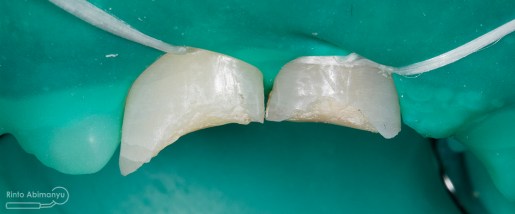

Begini kondisi klinis saat datang…

Dari pemeriksaan radiografis lokasi fraktur menyerempet kamar pulpa pada ketiga gigi tersebut… Saya sampaikan kepada pasien bahwa ketiga gigi tersebut memerlukan perawatan saluran akar terlebih dahulu baru kemudian dilanjutkan dengan restorasi indirek… kenapa saya pilih restorasi indirek? Pertimbangannya adalah sisa struktur mahkota gigi yang ada bila hanya di “sambung” dengan restorasi direk dalam jangka panjang rentan mengalami kerusakan, yang kedua pemilihan warna akan lebih maksimal pada kasus ini…. Pasien setuju dengan rencan perawatan yang saya jelaskan…

Untuk kunjungan pertama ini saya rencanakan melakukan perawatan saluran akar langsung pada dua gigi central… Saya pasang rubber dam untuk mengisolasi daerah kerja